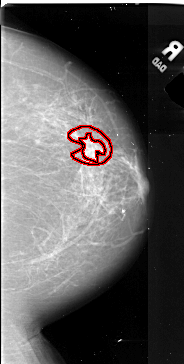

A_1069_1.LEFT_MLO

FILE: A_1069_1.LEFT_MLO.OVERLAY

TOTAL_ABNORMALITIES 2

ABNORMALITY 1

LESION_TYPE MASS SHAPE ROUND MARGINS SPICULATED

ASSESSMENT 5

SUBTLETY 5

PATHOLOGY MALIGNANT

TOTAL_OUTLINES 2